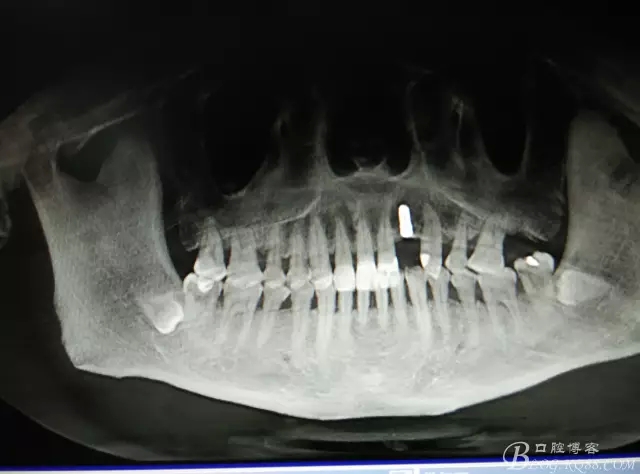

患者、楊xx、男、49歲。主訴:左側(cè)前牙拔除半年,活動(dòng)義齒修復(fù)四個(gè)月,要求種植修復(fù)。??茩z查:21缺失,牙槽粘膜厚度正常。CBCT檢查:高度16mm,寬度7mm.術(shù)前簽知情同意書。

圖1.術(shù)前的CBCT檢查:22缺失。